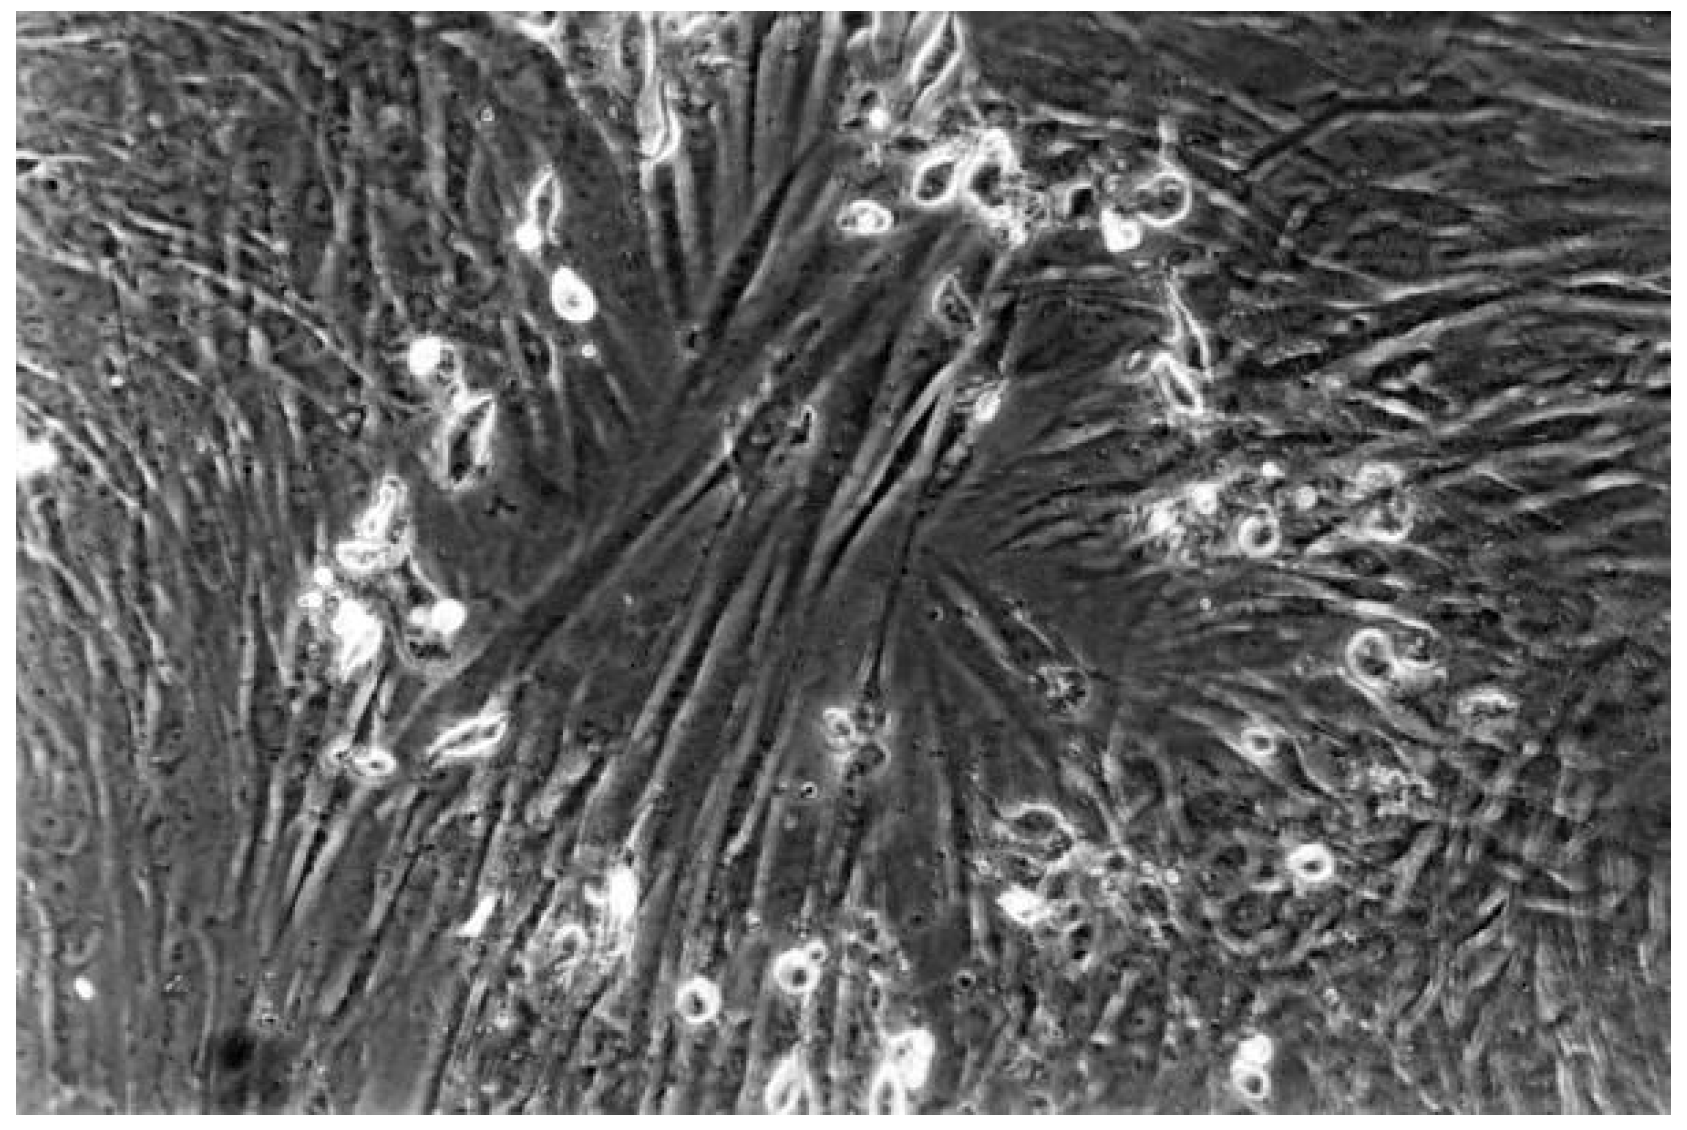

2.2.2. Qualitative Evaluation

| 1 | slight | Not more than 20% of the cells are round, loosely attached and without intracytoplasmatic granules, or show changes in morphology; occasional lysedcells are present; only slight growth inhibition observable |

| 2 | mild | Not more than 50% of the cells are round, devoid of intracytoplasmatic granules, no extensive cell lysis; not more than 50% growth inhibition observable |

| 3 | moderate | Not more than 70% of the cell layers contain rounded cells or are lysed; cell layers not completely destroyed, but more than 50% growth inhibition observable |

| 4 | severe | Nearly complete or complete destruction of the cell layers |